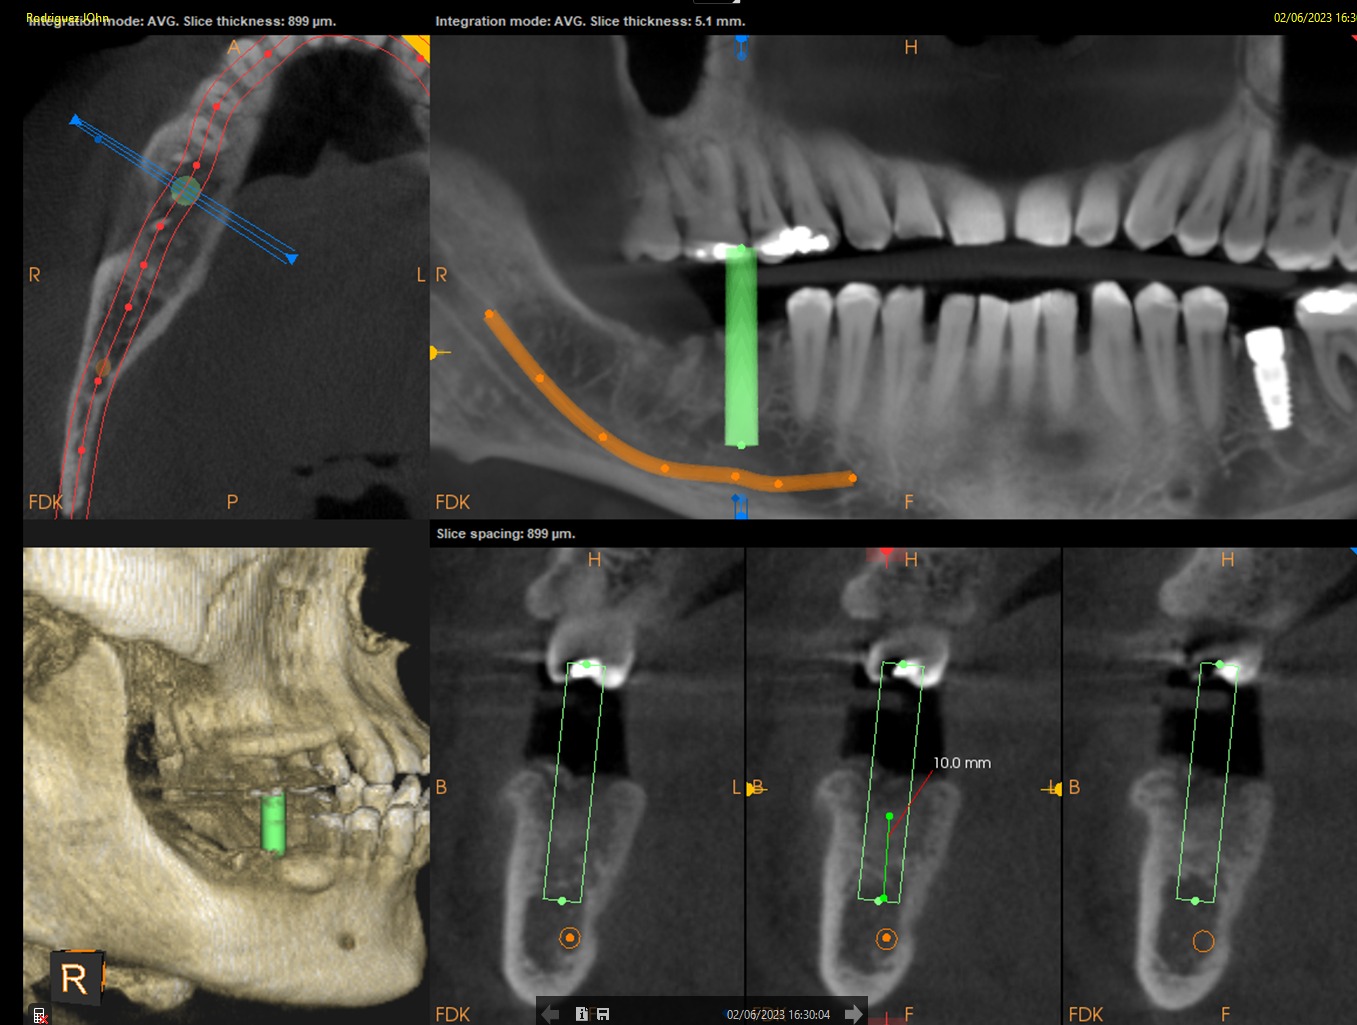

INITIAL STATE

CBCT imaging was used for precise implant planning, including evaluation of bone volume and anatomical landmarks. Digital planning allowed optimal implant positioning to ensure long-term stability and prosthetic-driven placement. Intraoral and periapical images confirmed the clinical condition prior to surgical intervention.